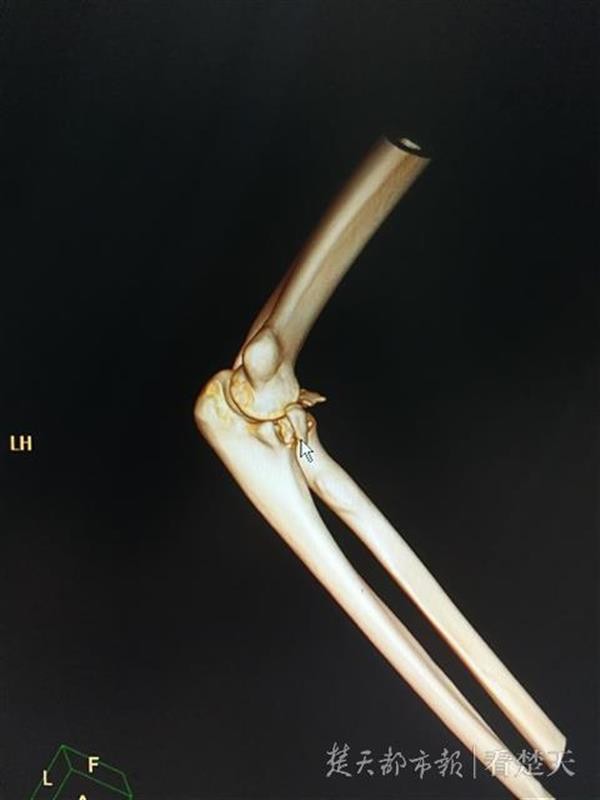

21日中午,武汉市第四医院骨科急诊内,20岁的李先生托着右手走进诊室,一旁的女友表情有些许尴尬。接诊医生黄振峰一眼就看出,李先生右手肘畸形,初步判断他的手臂应该有骨折。而进一步的CT检查结果证实,李先生右手肘骨折伴脱位。

李先生骨折的手肘

“李先生伤情较重,除了骨折,韧带也受伤了。进行复位后,后期还需要手术治疗。”接诊医生黄振峰介绍称,以往遇见过因为“公主抱”导致腰部受伤的病人,但是手臂骨折的较为少见。除了体能问题,可能也跟李先生当时抱人的姿势有关。